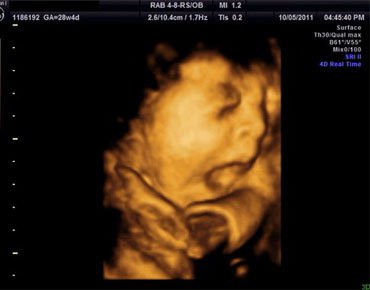

四维彩超的全称为四维彩色超声诊断仪,是目前世界上最先进的彩色超声设备,它可以做到表面显像,一些先天畸形疾病像是唇腭裂,脑膜膨出,脊柱裂等都可以清晰地反映出来,以便及时做治疗,提高优生率。

四维彩超自从应用于医疗后,就受到了众多新妈咪的青睐,因为它可以多角度,多方位的观察胎儿的生长发育情况,新妈咪可以通过设备看到宝宝的音容笑貌。

四维彩超属于表面成像,它的清晰度和准确度很高,可以为早期诊断先天性体表畸形和其他先天性疾病提供准确的科学依据,也可以分辨胎儿的性别,但是由于国家规定,若是用于非医学性操作的分辨胎儿性别是属于违法行为,因而医院做给孕妇做四维彩超时会主动避开胎儿的性别分辨。

做四维彩超在怀孕10周以上都是可以,一般最为合适是在怀孕24周-28周,因为24周左右时,正是胎儿大脑突飞猛进的发育时期,胎宝宝这个时期的结构已经形成。宝宝的大小及羊水适中,宝宝在宫内有较大的活动空间,胎儿骨骼回声影响比较小,做出来的图像也比较清晰。

四维彩色超声诊断仪是目前世界上最先进的彩色超声设备。在受孕24-28周做四维彩超比较好,考虑到孕妇的个体差异,做彩超的具体时间还要与医生沟通,遵从医嘱时间。因为给胎儿做四维彩超基本没影响,所以做检查时,可以通过四维成像技术观察可爱的宝宝在子宫里的状态,可提前感受做母亲的快乐。

四维彩超是目前世界上最先进的彩色超声设备,其特点是即时立体成像、清晰准确。四维b超不仅可以把宝宝的即时动态传递给准妈妈、还可以观察到宝宝的活动图像和在妈妈肚子里的各种神态,而且胎儿的四肢及内脏也能直接观测到,出胎儿各器官的发育情况也可以立体显示出来,这样,一些先天性畸形可见被尽早的发现,比如:对胎儿唇裂、腭裂、骨骼发育异常、心血管畸形等,从而做出更准确的早期诊断。让胎儿可以健康的生长发育。